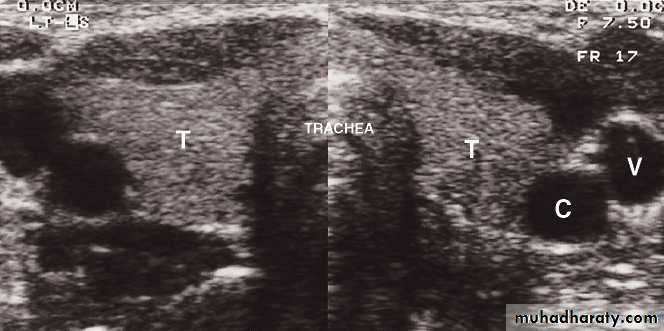

Neck

• Ultrasound: is recommended as the first line investigation, which may demonstrate the extent of the mass, LNs• Doppler studies: will indicate its vascularity

• CT : for cervical LNs enlargement or cervical mass (calcification)

• MRI: is the best method of imaging the neck because of the superior contrast between normal soft tissues and tumour

Thyroid imaging